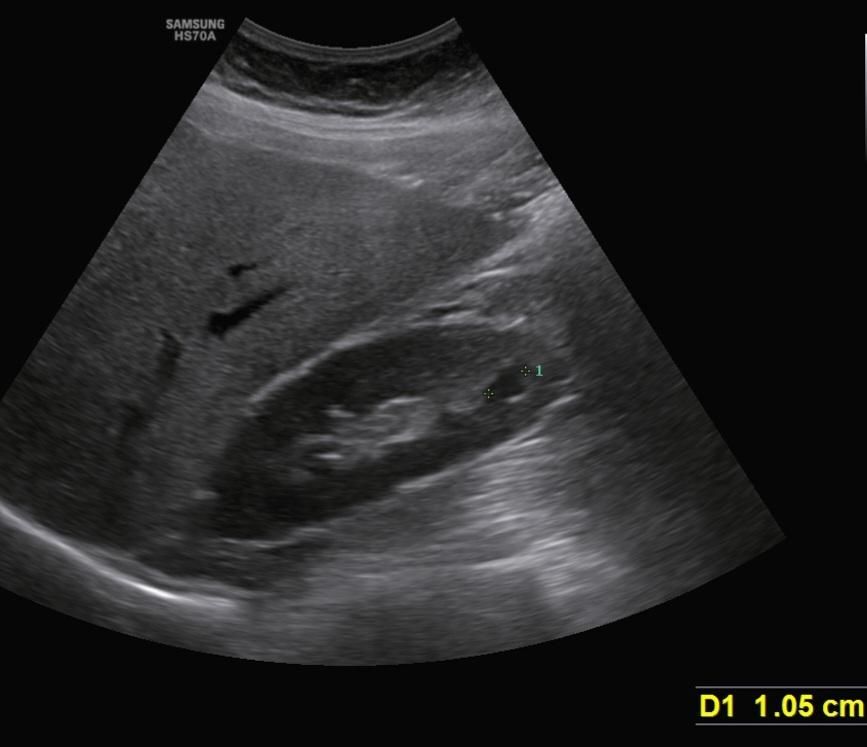

• 2번 째 사진

4. 크기 1.05 cm 정도

1cm대 작은 낭종은 대부분 임상적으로 문제 없습니다. 보통 증상도 없고 정기 추적만 권합니다.

다만, 초음파는 검사자·각도에 따라 해석이 달라질 수 있어 최종 평가는 영상의학과 판독지를 기준으로 보시는 게 가장 안전합니다. 판독지에 ‘simple cyst’ 또는 ‘Bosniak I’라면 크게 걱정하실 필요는 없습니다.